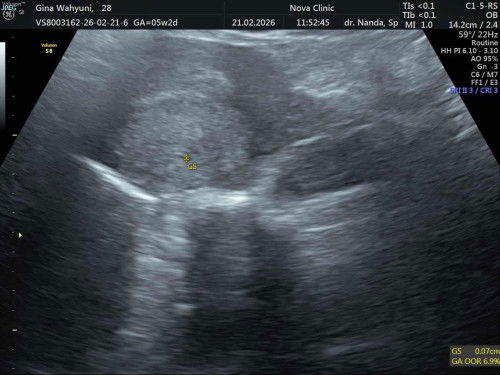

USG di 5week

Udh 5week wajar g ya belom terlihat pas usg #bantujawab #sharing